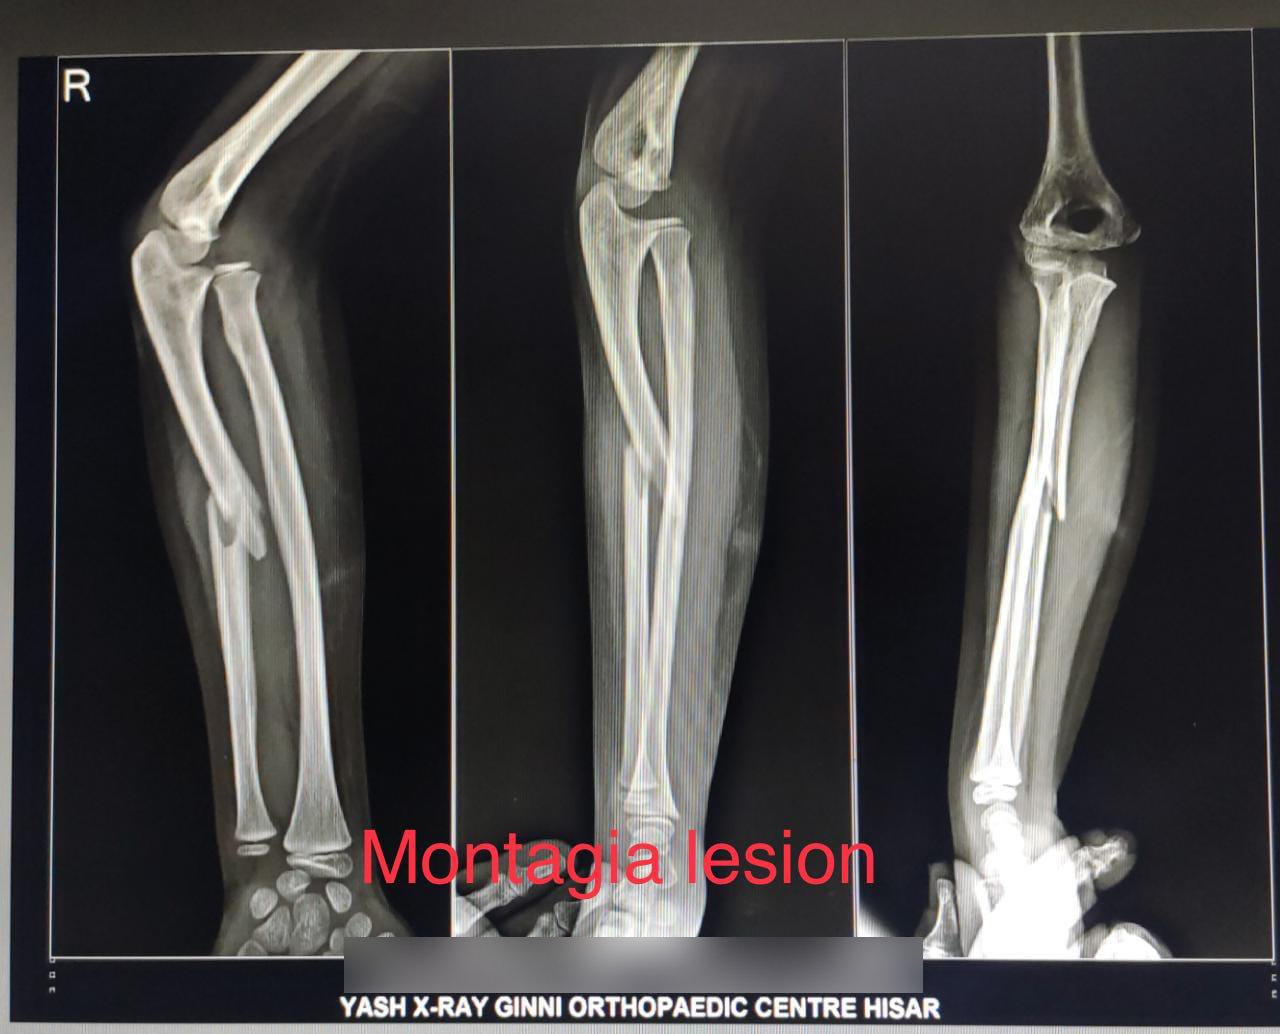

• X-ray: To classify the fracture